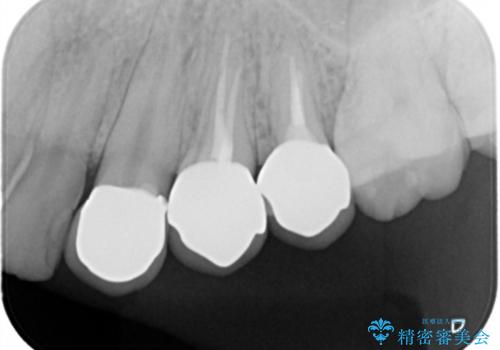

- 50.6万円(ジルコニアクラウン×3・仮歯×3・部分矯正)費用は治療当時の料金となります

当初、歯ぐきよりも深い虫歯の存在や、歯のポジションに問題がありましたがマルチブラケットを用いた部分矯正で行うことで歯の挺出同時に適切な位置へと歯を移動させ、歯周環境を整えたセラミック治療を行うことができました。